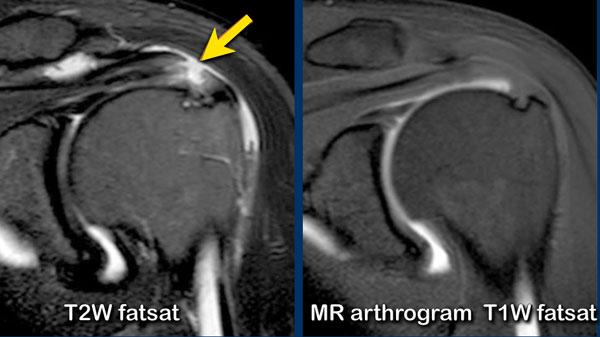

Đôi khi có thể khó phân biệt rách một phần với rách toàn bộ chiều dày.

Khi nhìn vào hình ảnh đầu tiên, tổn thương trông giống như rách một phần chiều dày phía mặt khớp.

Tuy nhiên, trên các lát cắt tiếp theo của chụp MRI khớp có thuốc tương phản từ, có thể thấy sự lan rộng không đều của thuốc tương phản từ từ mặt khớp ở bên trái đến mặt túi hoạt dịch ở bên phải, xác nhận đây là rách toàn bộ chiều dày.